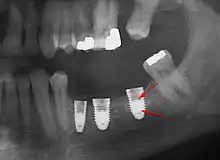

Fracture implant

Fracture of an implant and abutment screw is a catastrophic failure and the fixture cannot be salvaged.

Screw fracture

Fracture of abutment screws (arrow) in 3 implants required removal of the remainder of the screw and replacement.